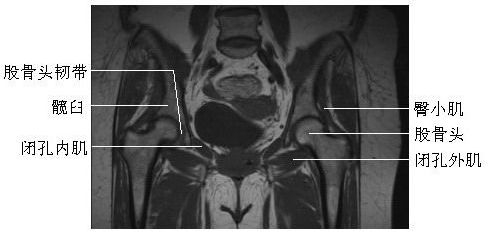

髋关节冠状面(一)